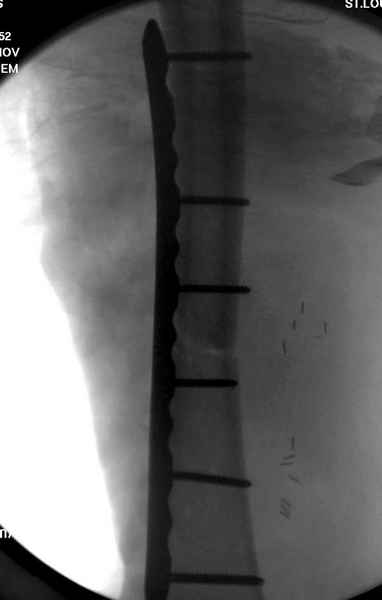

Больному с политравмой установлен наружный "spanning-bridging" фиксатор, после нескольких Irrigation&Debridment на фоне отрицательного посева из раны, через открытый участок установлен 4.5 mm Locking Plate.

На фоне фиксированного перелома бедра мероприятия по восстановлению мягкотканого покрова. Перелом голени зафиксирован после стабилизации бедра традиционным методом.